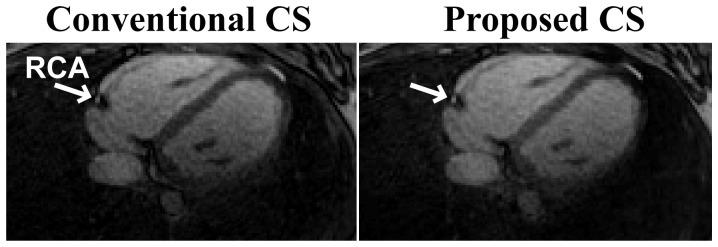

We sought to develop an alternative method for CS reconstruction that only requires two gridding and one regridding operation in total, irrespective of the number of iterations. This proposed technique is evaluated on phantom images and whole-heart coronary MRI acquired using 3D radial trajectories, and compared to conventional CS reconstruction using CG algorithms in terms of quantitative vessel sharpness, vessel length, computation time, and convergence rate.

Both CS reconstructions result in similar vessel length (P = 0.30) and vessel sharpness (P = 0.62). The per-iteration complexity of the proposed technique is approximately 3-fold lower than the conventional CS reconstruction (17.55 vs. 52.48 seconds in C++). Furthermore, for in-vivo datasets, the convergence rate of the proposed technique is faster (60±13 vs. 455±320 iterations) leading to a ∼23-fold reduction in reconstruction time.

The proposed reconstruction provides images of similar quality to the conventional CS technique in terms of removing artifacts, but at a much lower computational complexity.